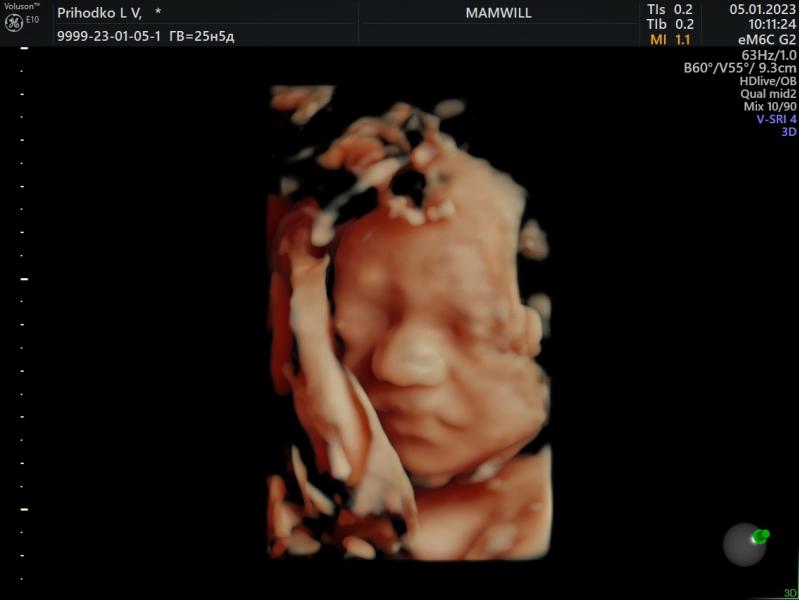

Наш долгожданный🤍

Были сегодня на встрече с мужем 🥰

Весит наш малыш 789 грамм

Сидим пока на попе с ногами на голове🙂

п.с. В конце его обидели уже🤧

05.01.2023